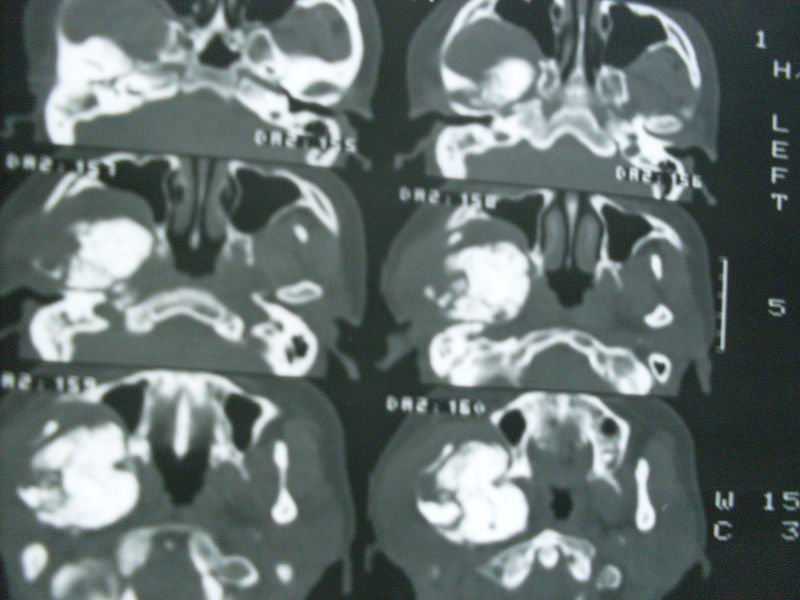

标题: CT12916:求助 F/44 右聂部肿痛一年余 [打印本页]

标题: CT12916:求助 F/44 右聂部肿痛一年余

是什么肿瘤

考虑为下颌骨升支旁软骨瘤或骨化性纤维瘤。

右侧下颌骨升支单骨病变,考虑非骨化纤维瘤可能。图片模糊,期等结果。

单骨病变,考虑骨化纤维瘤可能,与骨纤鉴别就此点